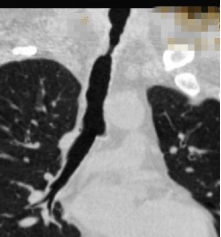

经过术前的充分准备,患者在全麻下,用可弯曲支气管镜引导插入法插入硬镜,通过高频电刀放射状切开狭窄环,再予气道球囊扩张器扩张气道置入硅酮支架,并置入喉罩复苏,最后成功为患者实施硬质支气管镜技术。术后,患者气道通畅,无呼吸困难、气促等症状出现,对比术前生活质量得到明显改善。

球囊扩张气道

患者术后情况